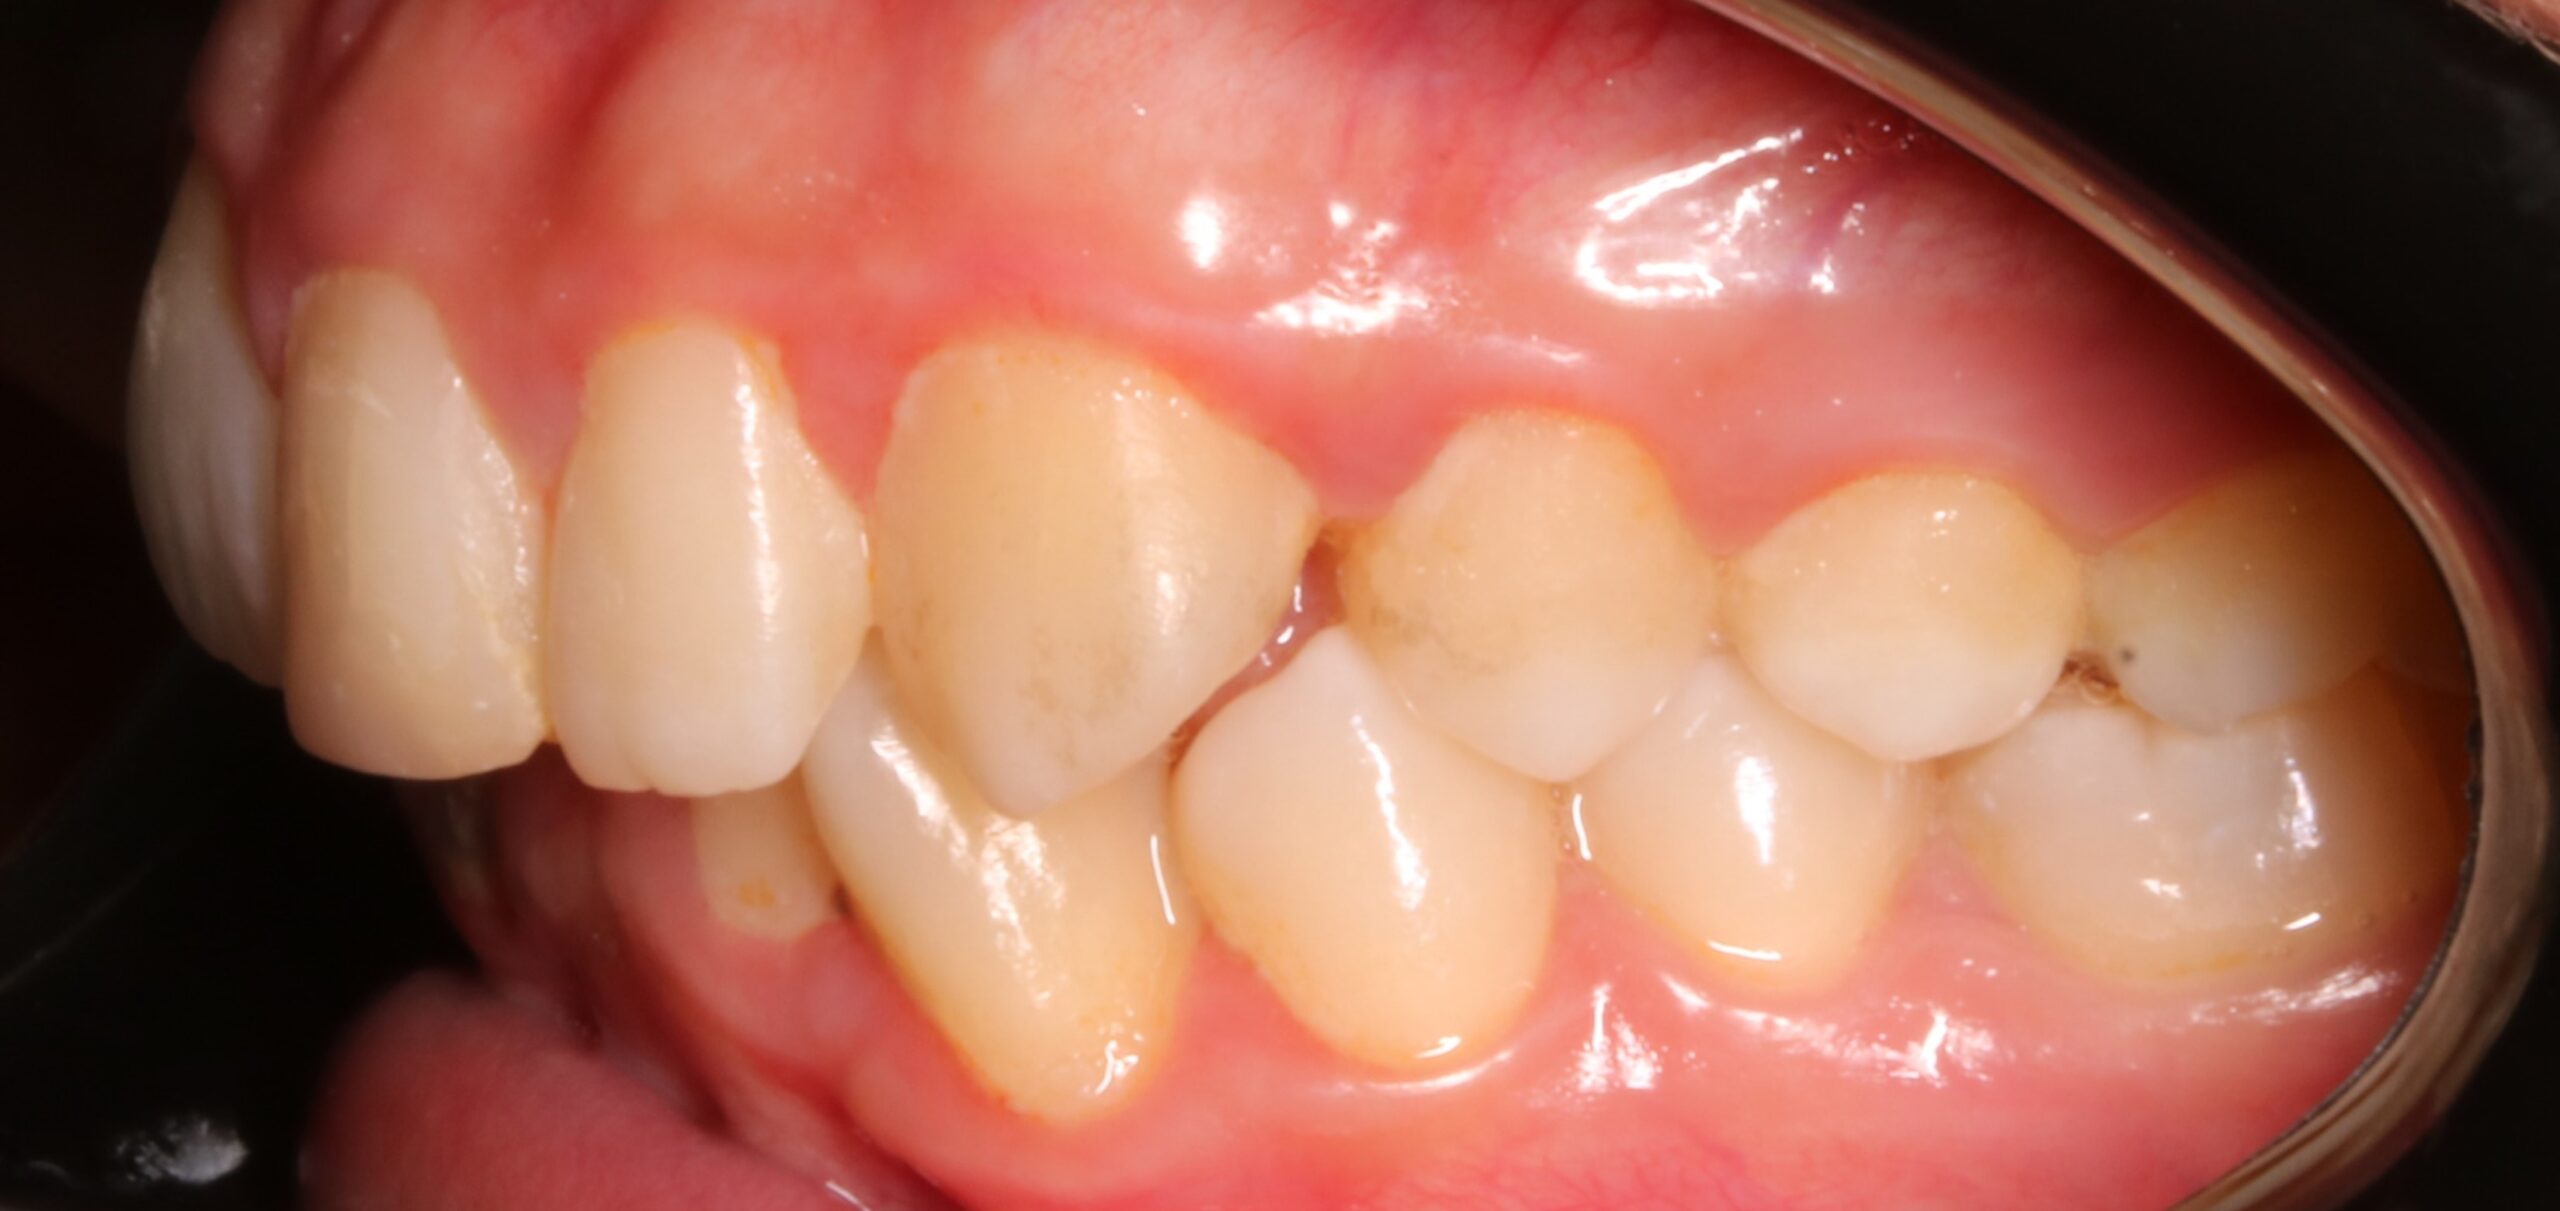

Como principal escollo, nos encontramos con una activa enfermedad periodontal y una deficiente higiene oral. También hay otros problemas secundarios que no hay que desdeñar: apiñamiento inferior con Bolton; leve apiñamiento anterosuperior; malposición de los cordales 48 y 38; rotación del 23; ligera clase II en el lado derecho entre otros. De primera hora se le comunicó a la paciente que antes de empezar el tratamiento de ortodoncia era necesario realizarse de periodoncia, y que después el/la profesional de esta disciplina, nos confirmara que podíamos empezar nuestro trabajo. También, avisamos de la importancia, de que durante el tratamiento, era necesario acudir al periodoncista cada 2 meses y mejorar la higiene oral.

En esta caso lo realizamos de la siguiente manera:

-Primero lo llevamos el canino hacia distal (para alejarlo de las raíces de los incisivos). De manera simultánea, el cantilever tenía asociado un movimiento de extrusión.

-Una vez el canino estaba extruido y alejado de las raíces, creamos el espacio necesario en la arcada y procedimos  a realizar la exodoncia del 53. A la par, que lo llevamos hacia vestibular con arcos de niti.

-En último lugar, y en fase de acero, usamos un brackets de -7 de torque, y con un auxiliar de torque, llevamos la raíz hacia vestibular.